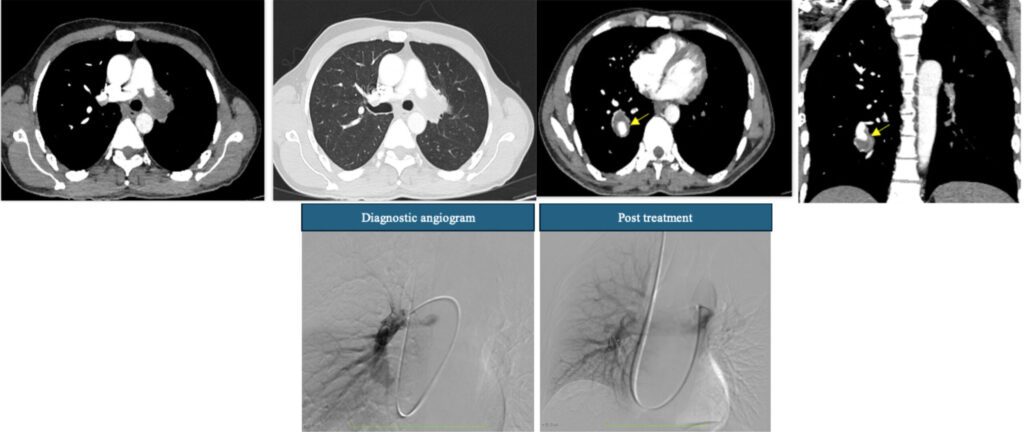

Case of the week Answer Key